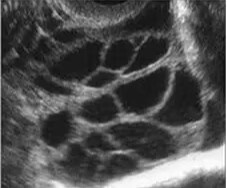

以卵巢过度刺激综合征(OHSS)为代表的卵巢高反应是促排卵过程中常见的并发症之一,以重度最为凶险。卵巢储备较好的年轻不孕症患者,尤其是PCOS妇女,是发生OHSS的高风险人群。AMH预测高反应的准确性高于FSH和AFC,诊断界值为>3.75 ng/ml。

(PCOS模式图及超声下影像)

(图:超声下OHSS的卵巢影像)